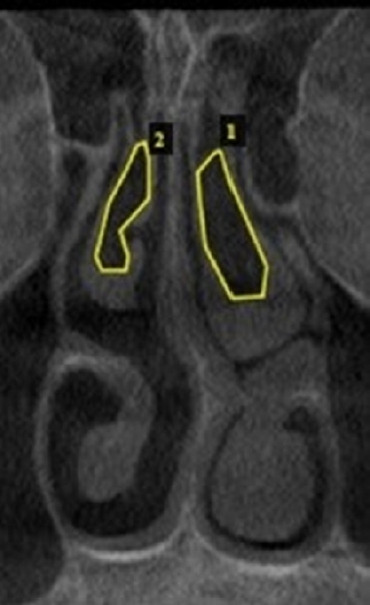

Background: Pneumatization of turbinates, also known as concha bullosa (CB), is associated with nasal septal deviation and sinonasal pathologies. This study aims to evaluate the performance of deep learning models in detecting CB in coronal cone-beam computed tomography (CBCT) images.

Methods: Standardized coronal images were obtained from 203 CBCT scans (83 with CB and 119 without CB) from the radiology archives of a dental teaching hospital. These scans underwent preprocessing through a hybridized contrast enhancement (CE) method using discrete wavelet transform (DWT). Of the 203 CBCT images, 162 were randomly assigned to the training set and 41 to the testing set. Initially, the images were enhanced using a CE technique before being input into pre-trained deep learning models, namely ResNet50, ResNet101, and MobileNet. The features extracted by each model were then flattened and input into a random forest (RF) classifier. In the subsequent phase, the CE technique was refined by incorporating DWT.